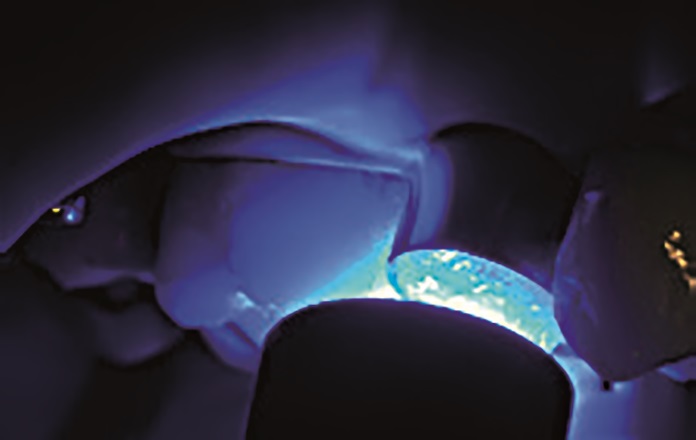

47‑letnia pacjentka zgłosiła się z powodu objawów zapalenia miazgi zęba 15. W badaniu wewnątrzustnym stwierdzono obecność starego wypełnienia amalgamatowego oraz złamanie guzka policzkowego zęba 15 (ryc. 1 i 2). W związku z tym na pierwszej wizycie przeprowadzono leczenie endodontyczne zęba 15 w znieczuleniu miejscowym (ryc. 3).